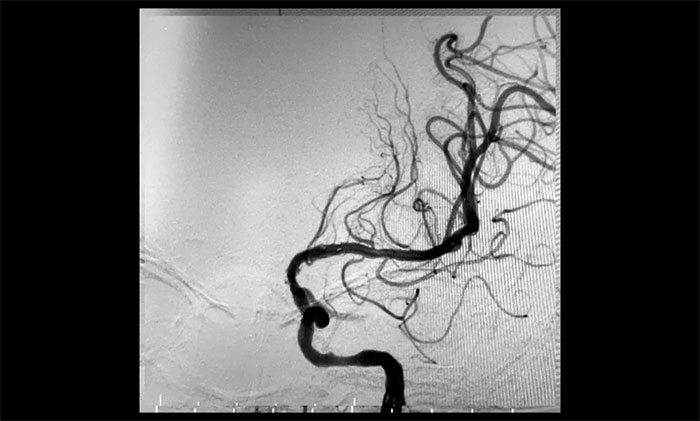

經(jīng)微導絲成功進入狹窄、閉塞頸內(nèi)動脈,在支架保護下,進行球囊逐段擴張,支架置入……,經(jīng)多次球囊擴張,置入支架后,造影顯示左頸內(nèi)動脈起始段狹窄明顯改善,左頸內(nèi)動脈顱內(nèi)段順利再通,左頸內(nèi)動脈眼動脈段、后交通段狹窄明顯改善。造影及3D造影見左頸總動脈、左頸內(nèi)動脈、左大腦中動脈顯影可,行支架CT見顱內(nèi)支架成形可,手術取得成功!

▲ 術后,右頸內(nèi)動脈起始段狹窄明顯改善

▲術后,左頸內(nèi)動脈起始段狹窄明顯改善,左頸內(nèi)動脈顱內(nèi)段順利再通,左頸內(nèi)動脈眼動脈段、后交通段狹窄明顯改善